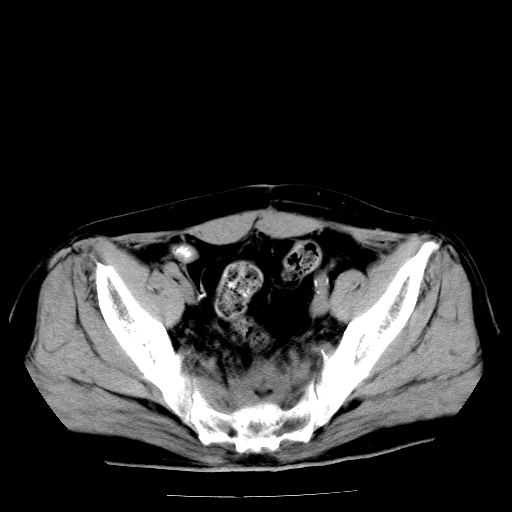

男,66岁,直肠癌术后一个月,化疗前ct检查。

直肠癌造瘘术后改变,周围淋巴结转移

前列腺肥大

直肠癌造瘘术后改变,盆腔多发淋巴结转移

直肠癌造瘘术后改变,直肠周围软组织增厚,盆腔多发淋巴结转移。前列腺肥大。